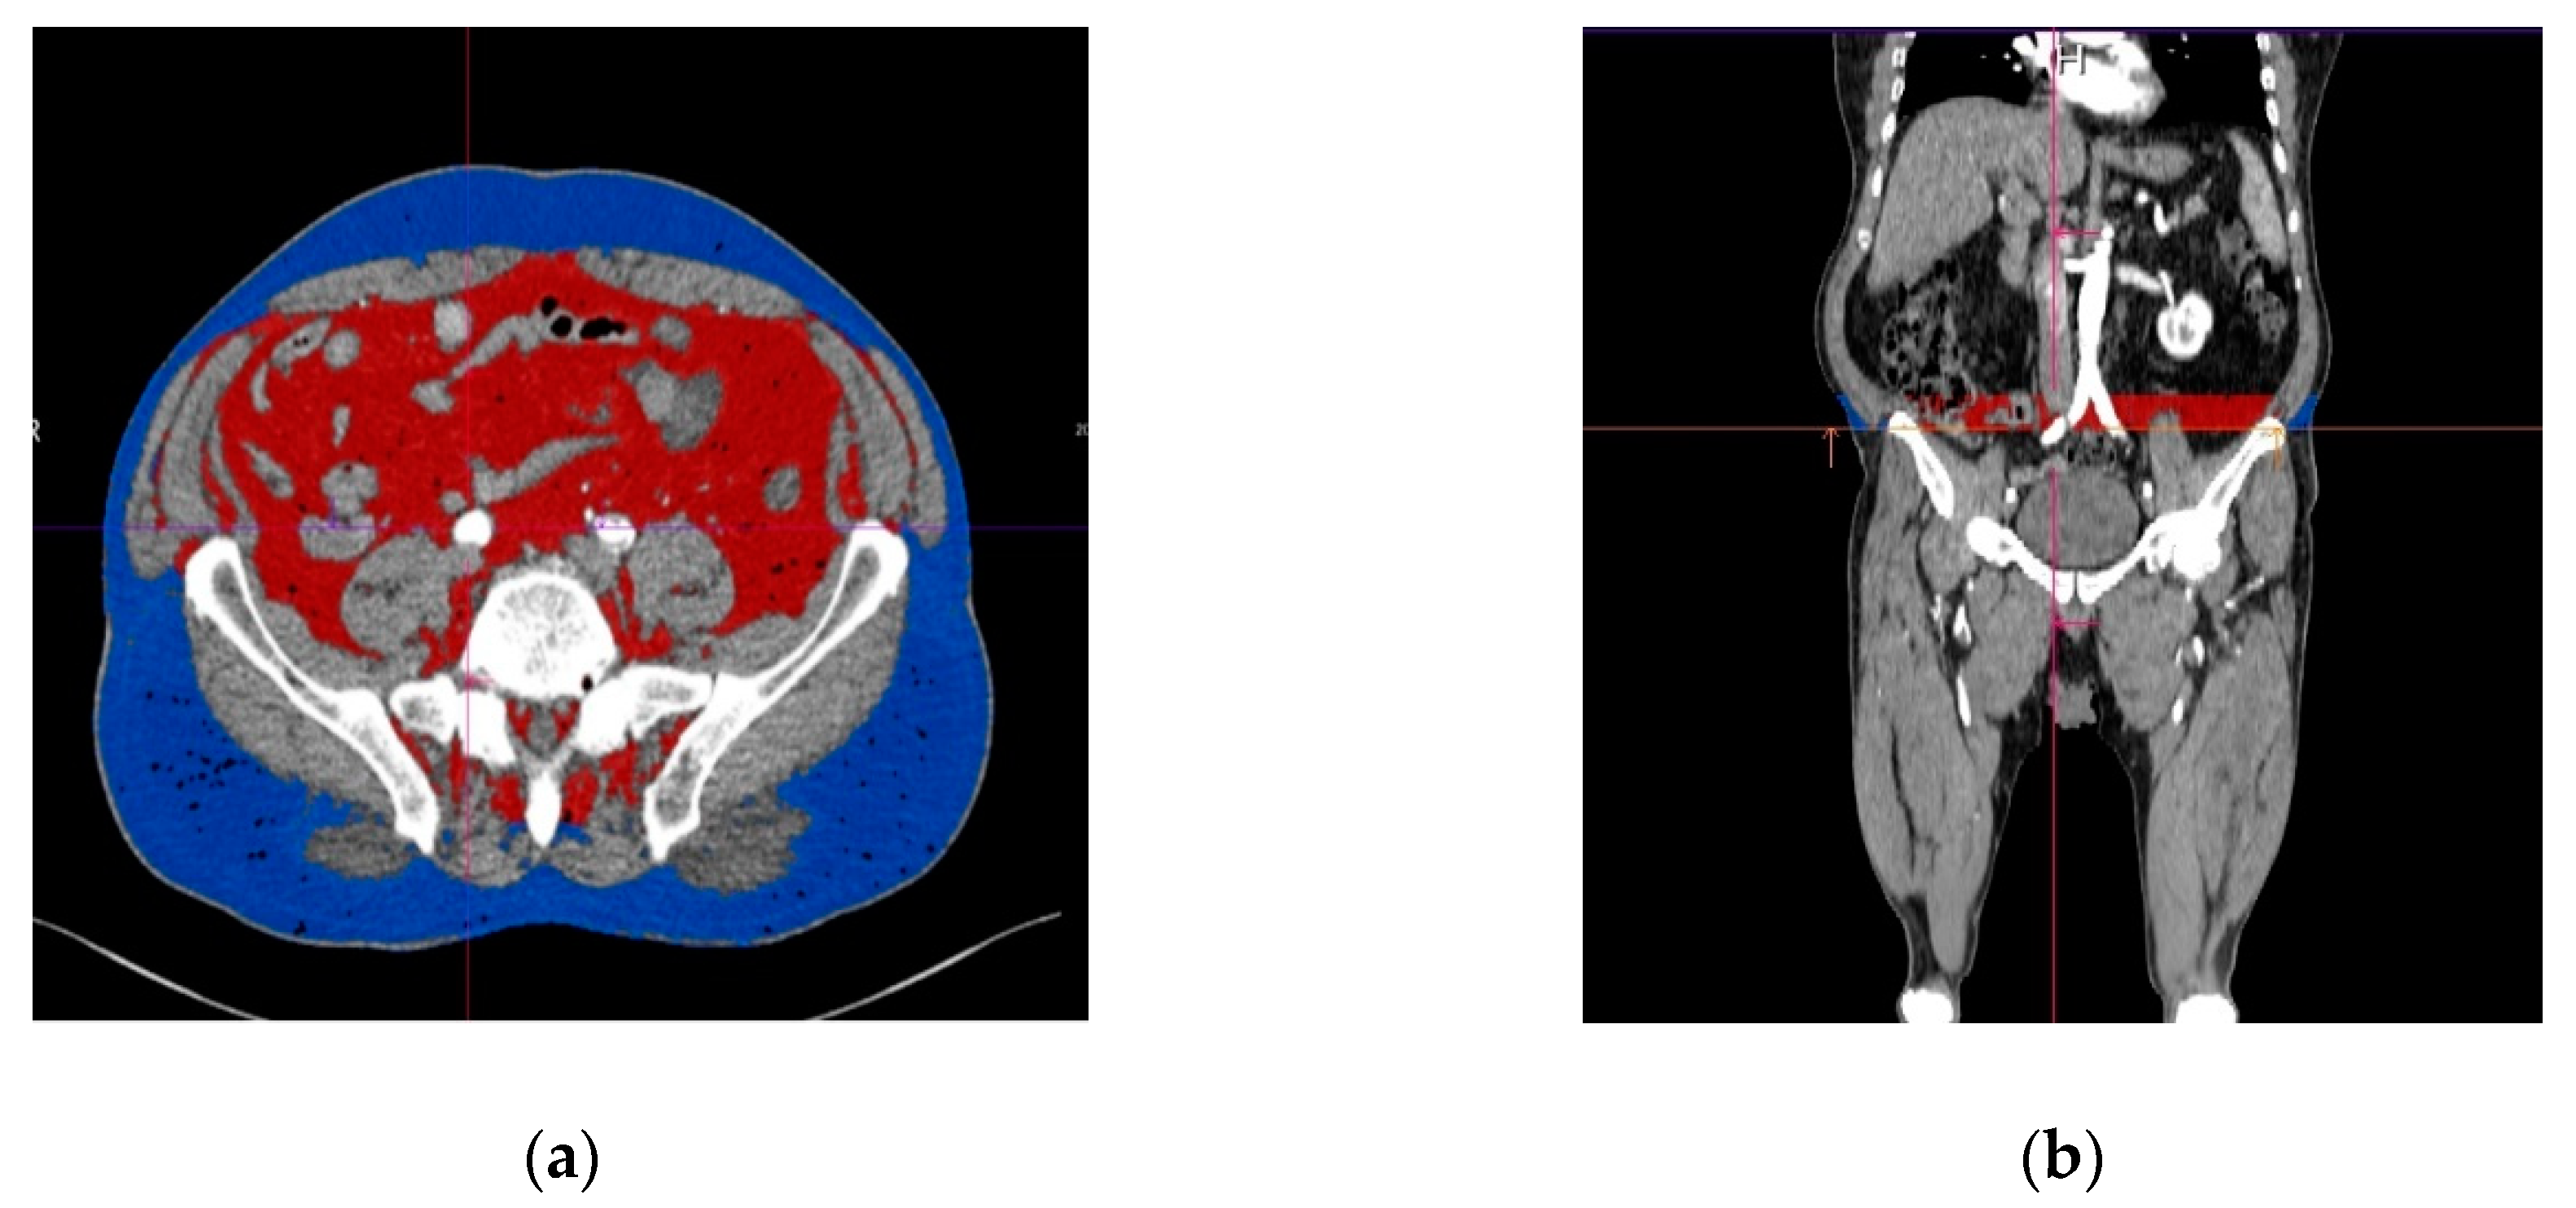

2.4. Assessment of The Subcutaneous and Visceral Adipose Tissue